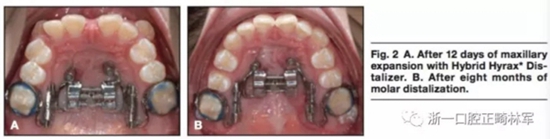

局麻下將兩枚2mm*9mm的微種植體植入鄰近腭中縫處。在上頜第一前磨牙處使用不銹鋼絲。使用聚乙烯硅氧烷上頜取模以制造Hybrid。局麻下翻開(kāi)粘骨膜瓣使用4枚皮質(zhì)釘以在下頜前牙放置鈦板。通過(guò)轉(zhuǎn)動(dòng)矢狀向的螺釘90°4次以激活擴(kuò)弓器,0.2mm每次,0.8mm每天。鈦板使用皮筋在兩側(cè)直接加400g前牽力。12天后,上頜前磨牙間橫向?qū)挾仍黾拥?mm。(圖2,A)矢狀螺釘在磨牙遠(yuǎn)移階段固定,每周激活雙側(cè)遠(yuǎn)移螺釘(0.2mm每周)。8個(gè)月后磨牙遠(yuǎn)移4mm(圖2B),該階段繼續(xù)掛皮筋。